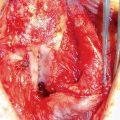

There is no clear consensus on stricture etiology and the success rate with respect to EPA. However, it is generally accepted that traumatic stricture due to perineal straddle injury is best treated by EPA. Suh et al. [38] reported that the recurrence rate was significantly higher in patients with nontraumatic causes (26.7%) than in the patients with traumatic cause (0%). The authors suggested that the most likely reason for the better results in the traumatic group is that spongiofibrosis developed from outside to inside, which makes it easier to identify the extent of stricture. On the contrary, spongiofibrosis propagated from inside to outside in urethral strictures of nontraumatic causes, especially those with iatrogenic or infectious causes. Therefore, the surgeon should convert an EPA to augmented anastomotic urethroplasty without hesitation if there is any concern about inadequate excision of unhealthy tissue.